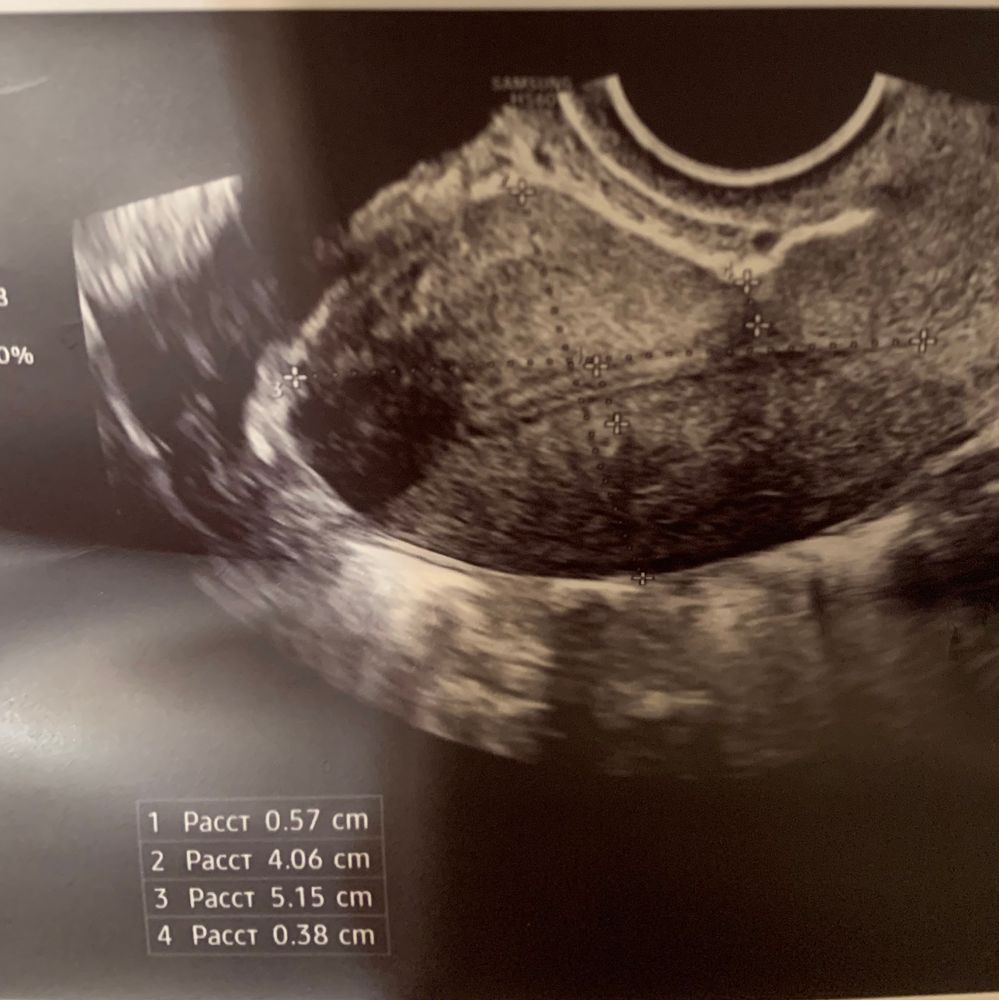

Была на узи на 8 день цикла. В левом яичнике, по словам врача, фолликулярная киста (около 20 мм). Эндометрий 5.4.

Буду мамой дочки , вероятнее всего, да это киста в стадии регресса, на это указывает и ее форма, включение и эндометрий. Фоликулярные кисты могут рассасывать несколько циклов.

Валерия , врач говорит, что это регрессирующая киста с прошлого цикла.